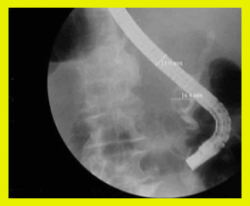

- בשיטה זו מחדירים אנדוסקופ דרך הפה לתריסריון, מזהים את הפפילה על-שם ואסר, ולתוכה מחדירים צנתר שדרכו מזריקים חומר ניגוד לדרכי המרה וללבלב. ההדגמה היא רנטגנית (תצלום 12.8- 11.8) וניתן לראות בה הרחבה של דרכי המרה, או אבנים (תצלום 13.8) או שאתות בדרכי המרה, או חסימות של דרכי המרה (תצלום 14.8). אפשר להדגים את כיס המרה והפתולוגיות שבתוכו.

- אם מודגמת אבן בדרכי המרה, אפשר לבצע בזמן הבדיקה:

- פפילוטומיה אנדוסקופית (Endoscopic papillotomy) - חיתוך של הפפילה לאורכה והרחבתה. הרחבה זו מאפשרת ניקוז טוב יותר של דרכי המרה, וכן היא מאפשרת לאבן שנתקעה במעבר הצר של הפפילה לעבור לתריסריון.

- שליפה של אבנים בעזרת מכשירים כגון Basket או ריסוק הגדולות שבהן ולאחר מכן שליפת הפירורים (תצלום 15.8).

- הכנסת נקז לדרכי המרה בחולים עם חסימה על מנת לנקז את דרכי המרה באופן זמני או קבוע (תצלום 16.8)